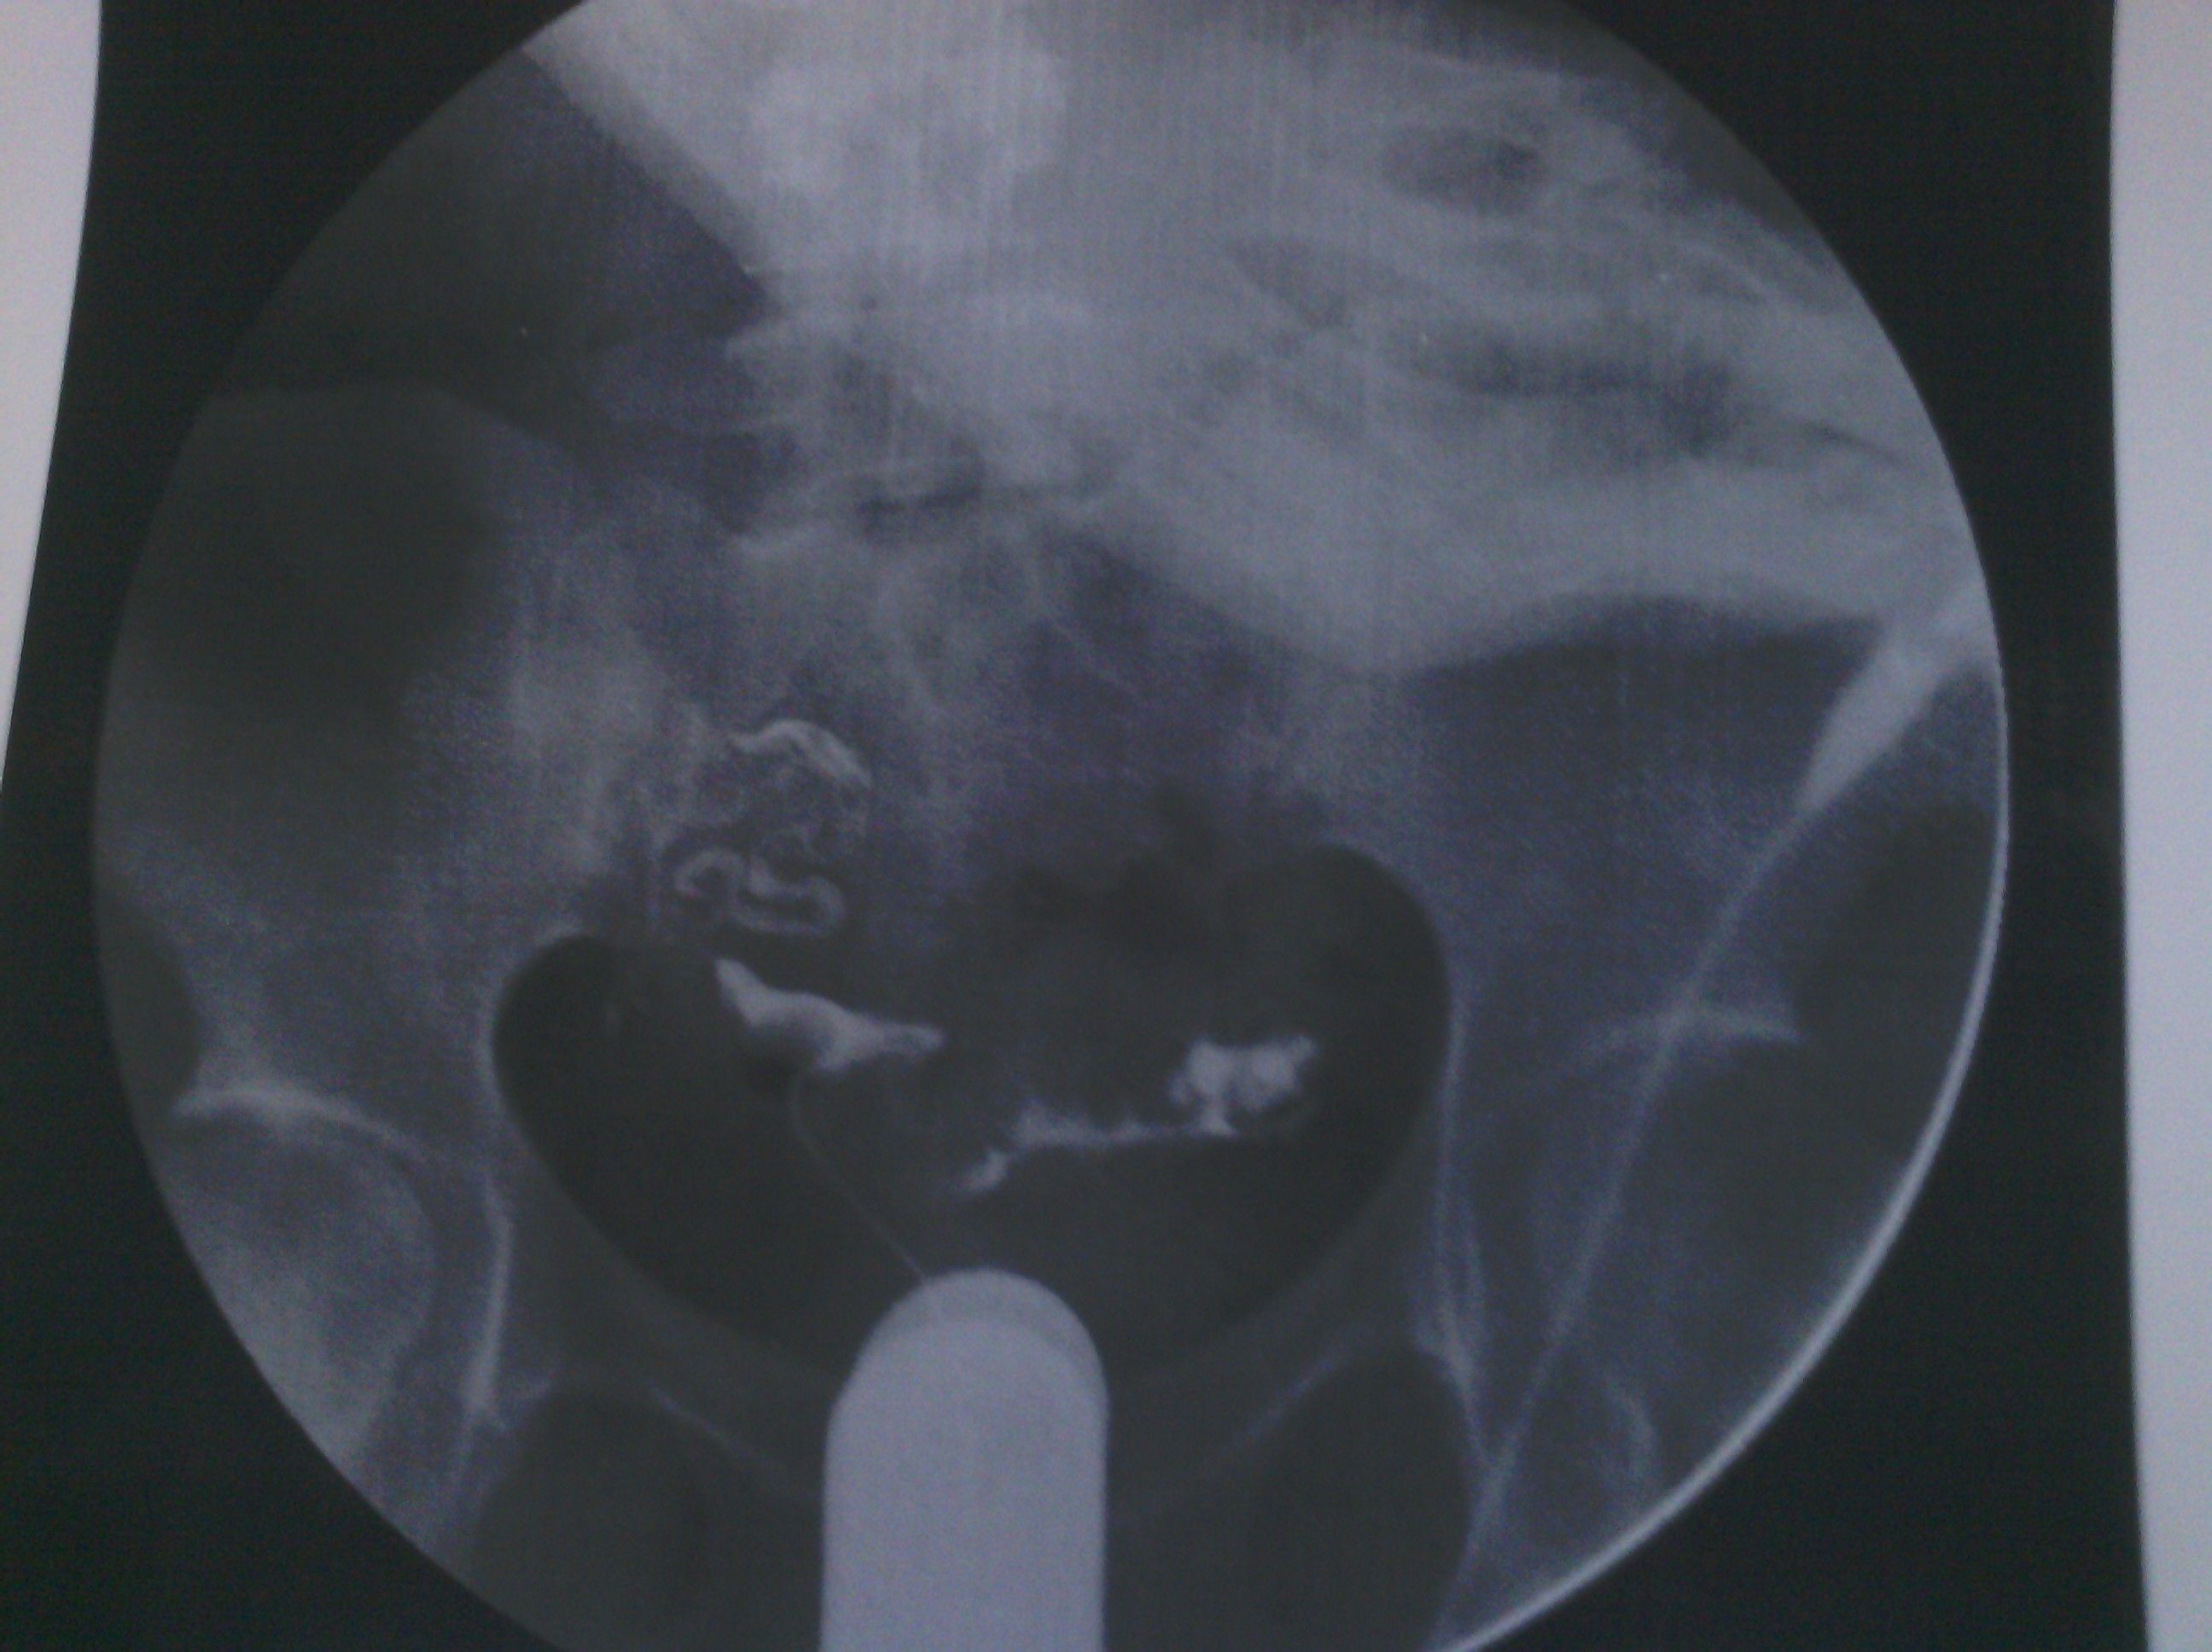

最新输卵管造影图片,麻烦各位大侠帮忙看看,纠结中 各位好,这是我11月6日做的输卵管造影图片,麻烦给看看现在是什么情况。在医院光说通而不畅有粘连,也没说哪个部位粘连,具体的是哪个部位有毛病呢?是间质部,峡部或是壶部。说少量弥散,然而弥散的片子也没延迟拍摄,是造影后直接就出来了,那判断的标准准确吗?看了好几年的病了,慕名到哪个医院去了,都没给过我合理化的建议,都是到哪家,哪家哪个拿手就推荐你做哪个,我现在看见医院两个字就想吐。我就是想,死,我也得死个明白。麻烦各位好心人看看我的片子给我一个合理化建议。现在的输卵管造影是个什么情况应该怎样治疗,在此拜谢各位了。我没啥财富值,对不起各位了。望能看片子解释一二,不胜感激。 点击展开 母婴用户710320885 2013-11-09 08:05 为您推荐: 其他回答 片子没标左右 所以我不清楚是哪边。 可以告诉你的是 面对我左边的输卵管走形上举,有黏连。面对右边的输卵管扭曲扩张。整个状况不是很乐观,具体治疗请咨询妇产科医生。 匿名用户 2013-11-11 14:28 相关问题 求讲解输卵管造影图片 妇科医生专家好:请帮忙看看这份“子宫输卵管造影检查报告”: 帮忙看看造影的报告,双侧输卵管炎不能怀孕了吗?

各位好,这是我11月6日做的输卵管造影图片,麻烦给看看现在是什么情况。在医院光说通而不畅有粘连,也没说哪个部位粘连,具体的是哪个部位有毛病呢?是间质部,峡部或是壶部。说少量弥散,然而弥散的片子也没延迟拍摄,是造影后直接就出来了,那判断的标准准确吗?看了好几年的病了,慕名到哪个医院去了,都没给过我合理化的建议,都是到哪家,哪家哪个拿手就推荐你做哪个,我现在看见医院两个字就想吐。我就是想,死,我也得死个明白。麻烦各位好心人看看我的片子给我一个合理化建议。现在的输卵管造影是个什么情况应该怎样治疗,在此拜谢各位了。我没啥财富值,对不起各位了。望能看片子解释一二,不胜感激。